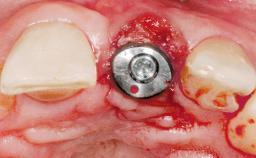

A 30-year-old female patient was referred to the office for the treatment of tooth 11. Her chief concern at the initial visit was to inquire, “Why is my tooth pink?” Upon clinical examination, it was determined that tooth 11 had a previous history of trauma and that the clinical crown had become noticeably pink in color as a result of internal resorption. This diagnosis was confirmed radiographically, indicating a large radiolucency involving the central and distal portions of the clinical crown. It was determined that restoration of this tooth was not possible, and that extraction was indicated. The presence of a mid-line diastema, which the patient wanted to reproduce, directed the treatment plan for tooth replacement utilizing a dental implant.

Placement Protocol Immediate implant placement

Tooth Site Maxillary incisor or canine

Socket Morphology Single-root socket

Socket Integrity Sufficient, with intact bone walls